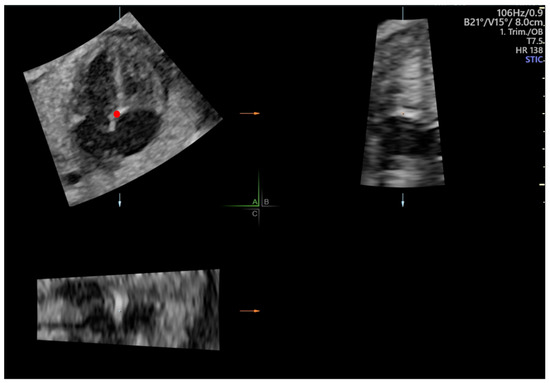

2.3. Speckle Tracking Analysis